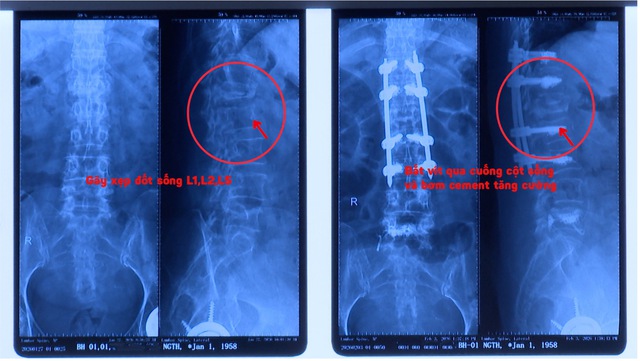

Theo khai thác bệnh sử, khoảng 2 tháng trước khi nhập viện, bệnh nhân bị trượt té, va chạm mạnh vùng mông xuống mặt đất. Sau đó, bệnh nhân điều trị nội trú tại cơ sở y tế tuyến trước và được chẩn đoán xẹp thân đốt sống thắt lưng L1, L2 và L5. Tuy nhiên, sau khi xuất viện, tình trạng đau vùng thắt lưng không cải thiện mà ngày càng tăng, ảnh hưởng nghiêm trọng đến sinh hoạt hằng ngày.

Sau đó, bệnh nhân đến Bệnh viện Đại học Nam Cần Thơ để thăm khám và điều trị. Qua thăm khám lâm sàng, bệnh nhân tỉnh táo, tiếp xúc tốt; đau nhiều vùng cột sống thắt lưng; ấn đau rõ tại các đốt sống L1, L5; có cảm giác tê hai chân, yếu hai chi dưới và vận động hạn chế. Kết quả MRI cột sống thắt lưng ghi nhận: thoái hóa cột sống thắt lưng, gãy xẹp thân đốt sống L1, L2, L5 kèm phù tủy xương, đặc biệt, đốt sống L1 xẹp gây chèn ép tủy.

Phim trước và sau phẫu thuật

Bệnh nhân được hội chẩn với chẩn đoán: gãy xẹp L1 chèn ép tủy/xẹp L5/loãng xương và chỉ định phẫu thuật. Đây là trường hợp cần can thiệp phẫu thuật do đốt sống L1 xẹp gây chèn ép tủy sống. Nếu không xử trí kịp thời, tình trạng có thể dẫn đến tổn thương tủy sống tiến triển và nguy cơ liệt hai chi dưới.

Sau đó, bệnh nhân được tiến hành phẫu thuật bắt vít qua cuống cột sống thắt lưng qua da có bơm cement tăng cường, kết hợp giải áp tủy sống. Dù là một ca bệnh phức tạp và nhiều thách thức, các bác sĩ đã nỗ lực phối hợp chuyên môn chặt chẽ để thực hiện phẫu thuật thành công.